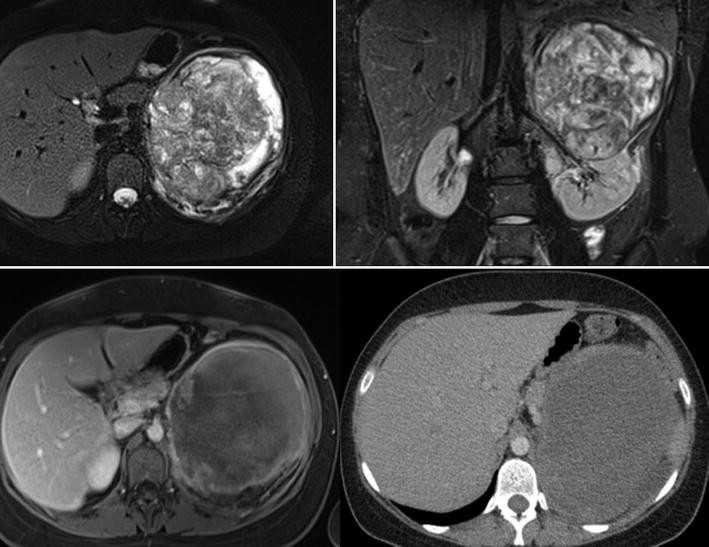

Nierenzyste Diagnose Bosniak Klassifikation Und Therapie

Ct Und Mrt Der Niere Des Retroperitoneums Und Der Harnblase